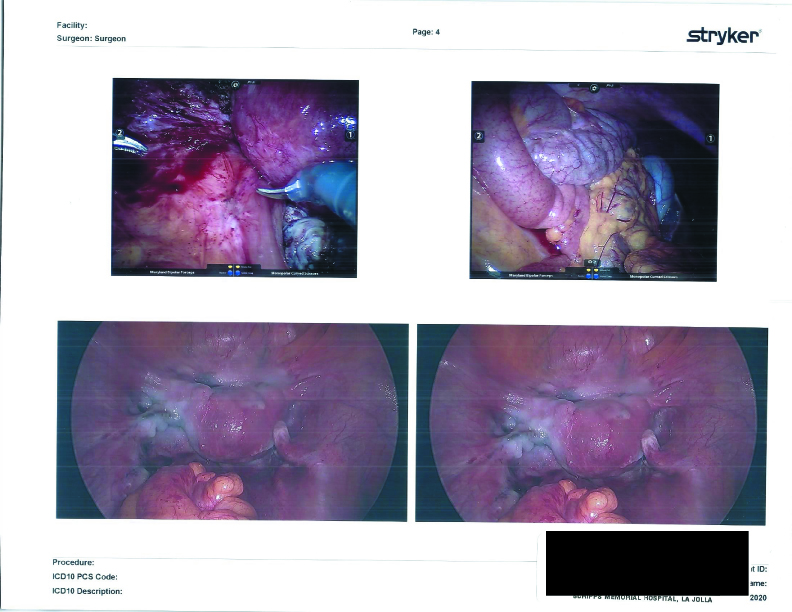

Now, back to the guts. On my distal sigmoid colon, he found a patch of Endometriosis, which he notes as “a deep penetrating cluster of endometriosis lesion.” In my post-op appointment, he classified it as a nodule of Endometriosis, and said it looked like Deep Infiltrating Endometriosis to him. Unfortunately, due to the high risks involved in cutting that deeply into the intestine without a full bowel prep and a colo-rectal surgeon on hand, he took note (and photographs) of its positioning and opted not to remove the nodule. More on this will be addressed in “The Plan” section below.

He then removed the cyst on my right ovary and was able to save the ovary.

He thoroughly checked the rest of my pelvic cavity and found no further Endometriosis. He freed all adhesions and restored any wonky anatomy to its rightful place.

Before closing me up, a bag was placed inside my pelvic cavity, Lefty was tossed inside the pouch, and all was pulled out of my body. YAY! Good riddance! All of the CO2 gas was expelled from my pelvic cavity. And I mean ALL of it. I had ZERO occurence of post-laparoscopy shoulder pain due to any remaining CO2 gas. NONE. Dr. Kurtulus and I refer to it as the “Lisa Special,” where extra time and care is taken to make sure it’s all out. He does it for all of his patients and one day I hope he publishes the importance of taking extra time and effort to teach other surgeons. With all the gas gone, I was sealed up.

Also, per tradition, he took a look inside my bladder in search of any signs of Endometriosis or Interstitial Cystitis or anything else that should not be there. Clean as a whistle and beautifully pink.

Surgical Photographs

As promised here are the surgery photographs! Please be aware that the scans are low quality; the Endo on the colon is MUCH more visible, almost a dark purple blotch on the hard printouts. If I get higher-quality scans, I’ll be sure to update these. You can click on them for a larger image.